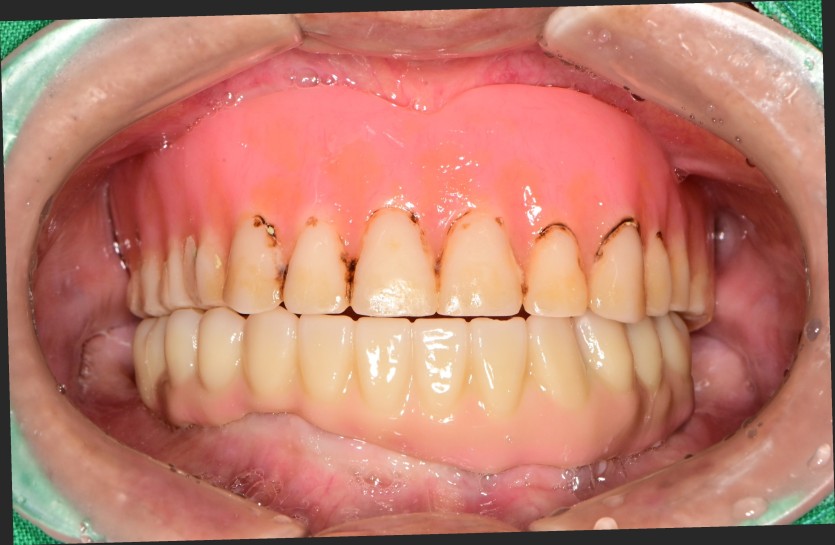

만 82세 하악 풀아치 증례

하악 풀아치 증례입니다.

(상악 기존 틀니)

6개의 임플란트로 완성하였습니다.